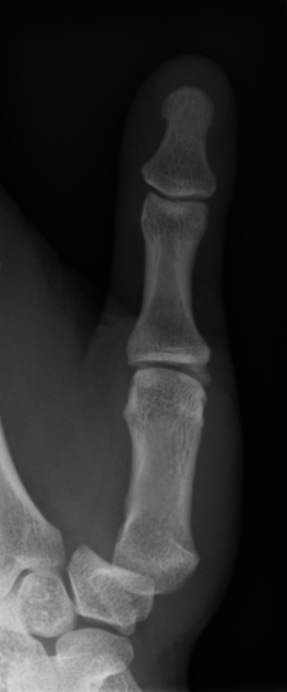

Female aged 28.

Fell on the outstetched hand. Considerable pain in and around the thumb metacarpal (MC)..

No localised wrist, nor snuff box, tenderness. A tender 1st MC with some swelling.

Is there a bone or joint abnormality present?